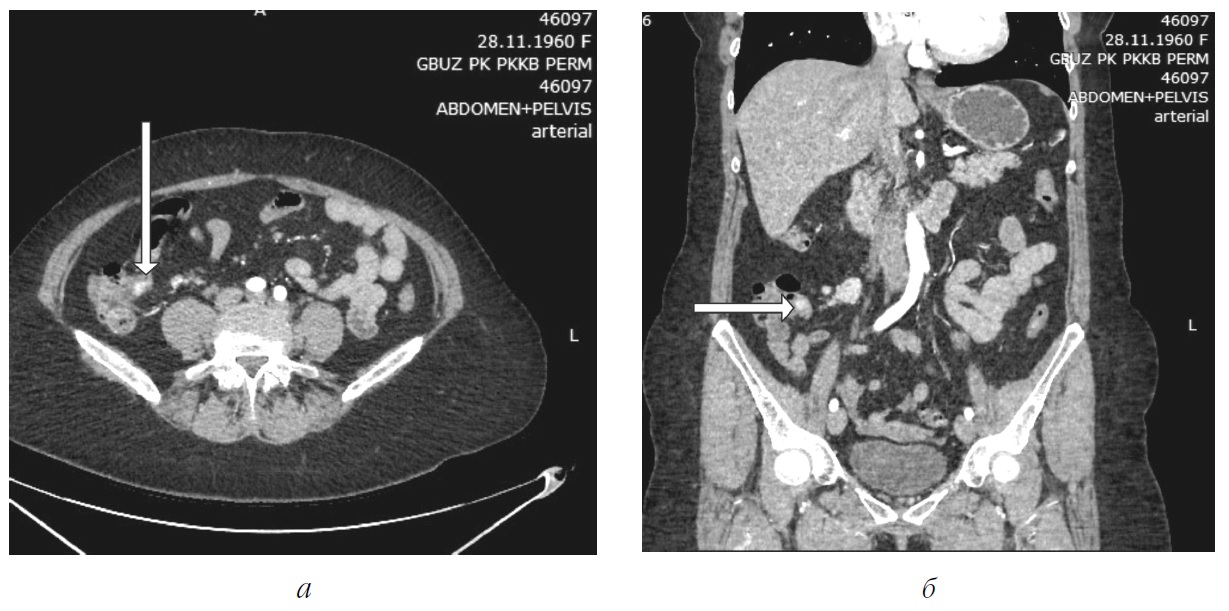

Рис. 2. Артериальная фаза. По брыжейке тонкой кишки в области илеоцекального угла обнаружены два увеличенных лимфатических узлов, самый крупных из которых имел размеры 25´18 мм: а – МСКТ-ангиография. Аксиальный срез; б – МСКТ-ангиография. Коронарный срез

По брыжейке тонкой кишки в области илеоцекального угла найдена группа увеличенных лимфатических узлов, самый крупных из которых имел размеры 25´18 мм (рис. 1, б).

В представленном случае клинические проявления заболевания были неспецифическими, а обследование начато с недостаточно информативного метода – МСКТ без болюсного контрастирования, что привело к задержке постановки правильного диагноза на 7 месяцев. Обнаружение увеличенного лимфатического узла в брыжейке тонкой кишки было неправильно интерпретировано, дополнительно проведено только эндоскопическое исследование желудка и толстой кишки. На низкую чувствительность МСКТ без болюсного усиления указывает A.K. Clift et al., поскольку НЭО тонкой кишки обычно имеют маленькие размеры [7]. При МСКТ-ангиографии удалось диагностировать не только конгломерат лимфатических узлов в брыжейке тонкой кишки, но и обнаружить опухоль размерами 9´15 мм в стенке подвздошной кишки. Наибольшую чувствительность МСКТ-ангиографии в выявлении НЭО тонкой кишки отмечают многие авторы с колебаниями от 50 до 85 % [3, 7, 8]. Обнаружение увеличенных лимфатических узлов в брыжейке тонкой кишки при этом методе обследования достигает более 94 % [3, 7, 8]. Эндоскопическое исследование желудочно-кишечного тракта с использованием баллонной или капсульной энтероскопии в сочетании с МСКТ-ангиографией обладает самой высокой чувствительностью в выявлении НЭО тонкой кишки [7]. Проведение лапароскопии с биопсией лимфатического узла после его морфологического исследования позволило нам верифицировать диагноз до операции.